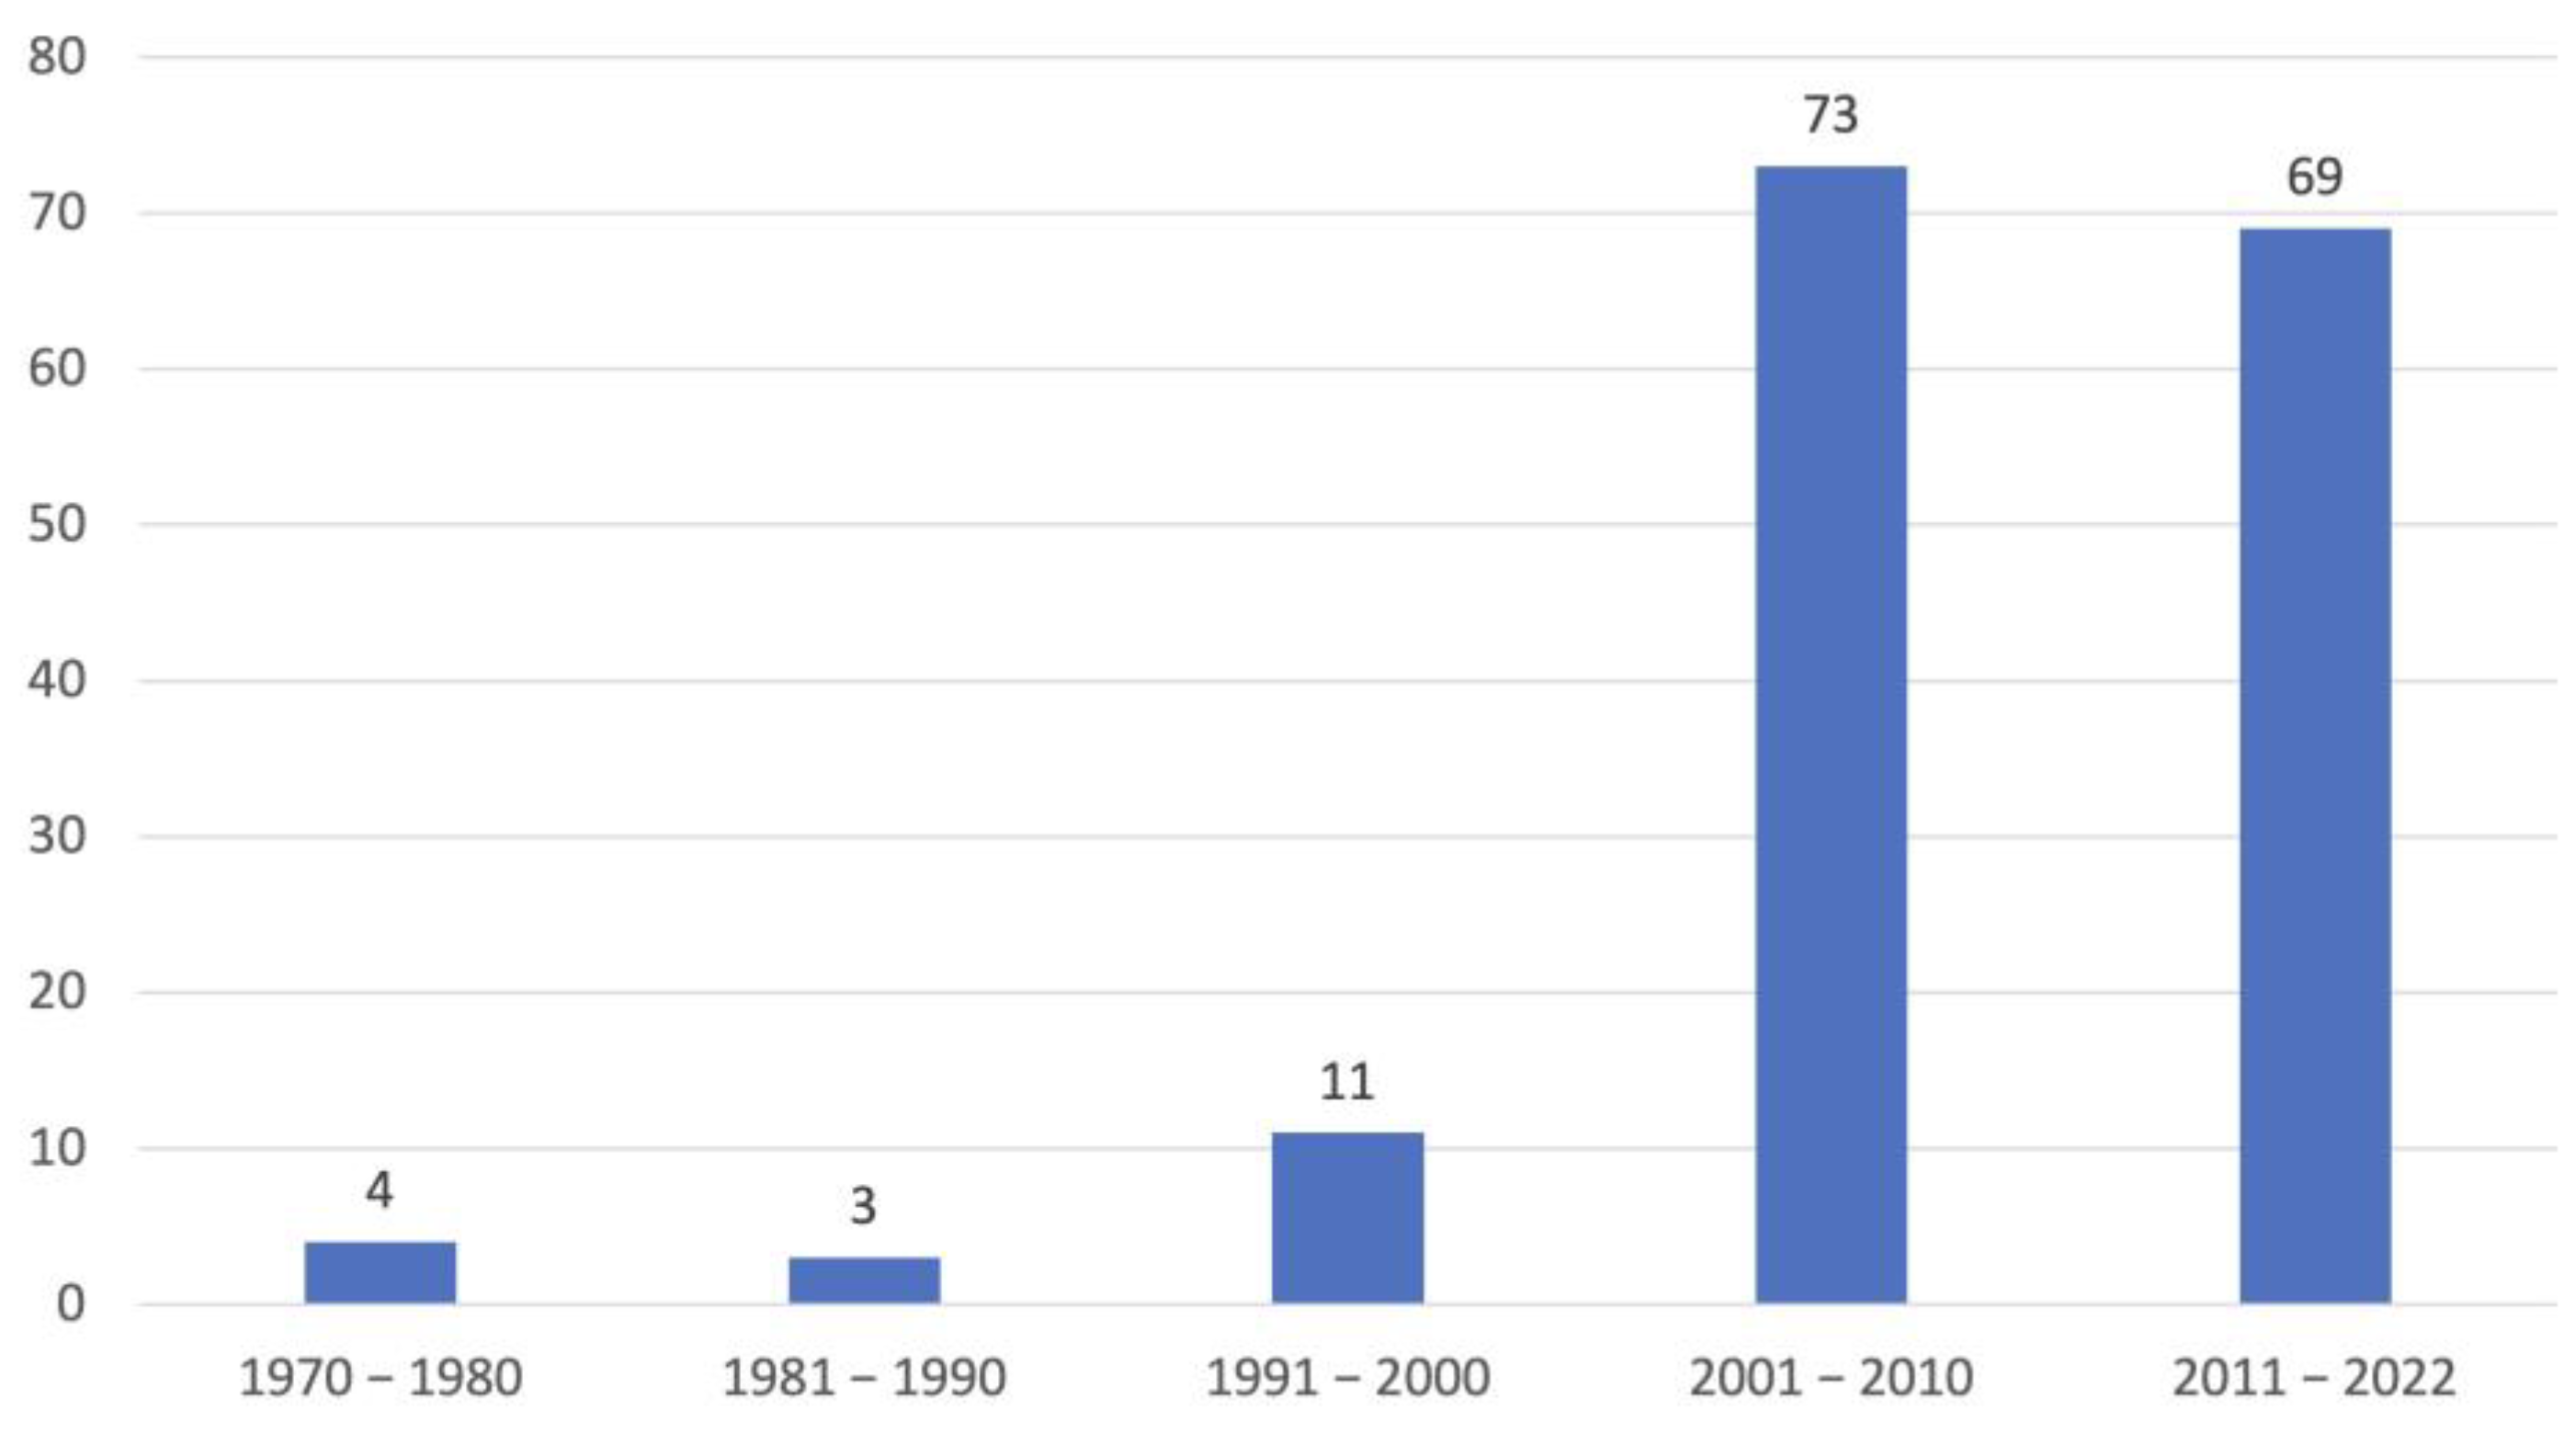

3.1. Dogs

3.2. Analysis of the Three Levels of Diagnostic Confidence